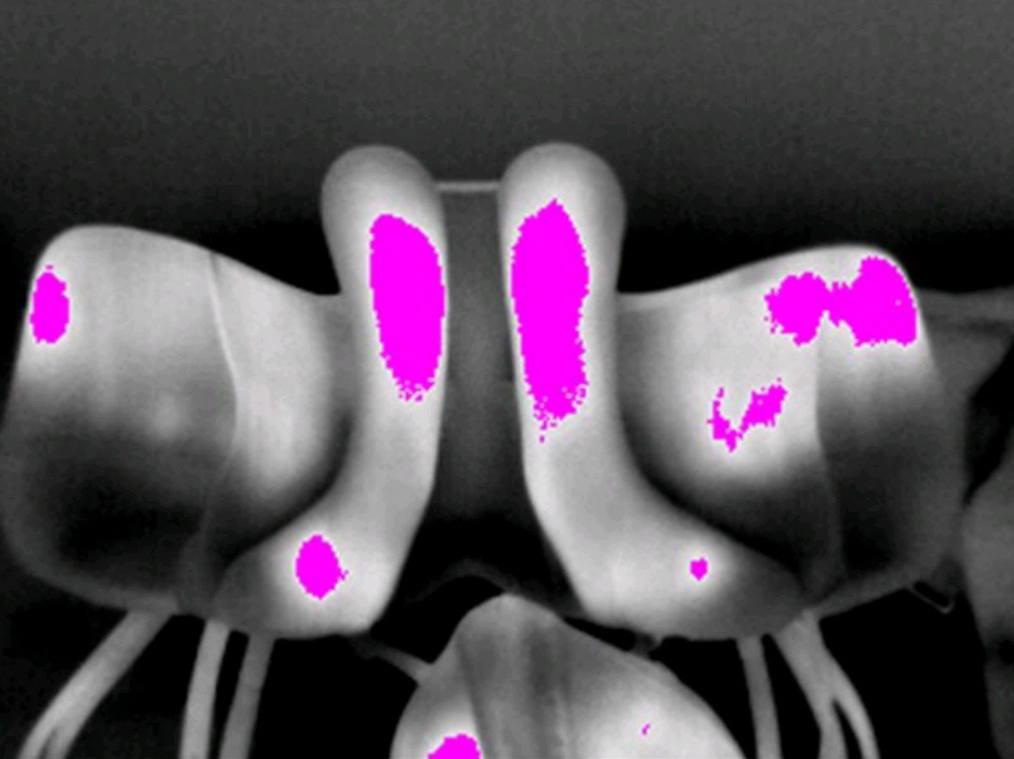

BESONDERHEIT SATTELTHERMOGRAFIE

VORTEILE

zuverlässiges Bild auch in der Bewegung, keine störenden Unterlagen (Impression Pad etc.), die die Bewegungen des Pferdes oder die Lage des Sattels beeinflussen, Zusammenarbeit mit Sattlern ist möglich

WAS LÄSST SICH FESTSTELLEN?

entzündete, gestresste und gereizte Bereiche

Asymmetrie im Bereich der Sattellage

Fehlerhafte Polsterung

Zu enger Wirbelkanal

Falscher Schwerpunkt

Druckspitze Steigbügelaufhängung

ABLAUF SATTELTHERMOGRAFIE

es werden Aufnahmen vor dem Reiten gemacht

Nach dem Reiten erneut

Ebenfalls Aufnahmen vom Sattel und dem Reiter

Ein schiefer Reiter und auch ein schiefes Pferd können die Aufnahmen beeinflussen. Daher ist der Reiter und auch das Pferd während des Reitens genau zu

beobachten. Idealerweise wird 20 Minuten in allen Gangarten am langen Zügel geritten.